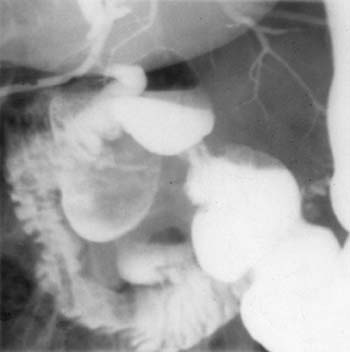

Сочетанные методы рентгеноконтрастного исследования в диагностике

заболеваний органов брюшной полости.

Рис. 2. Большой дивертикул сдавливает и смещает общий желчный проток.